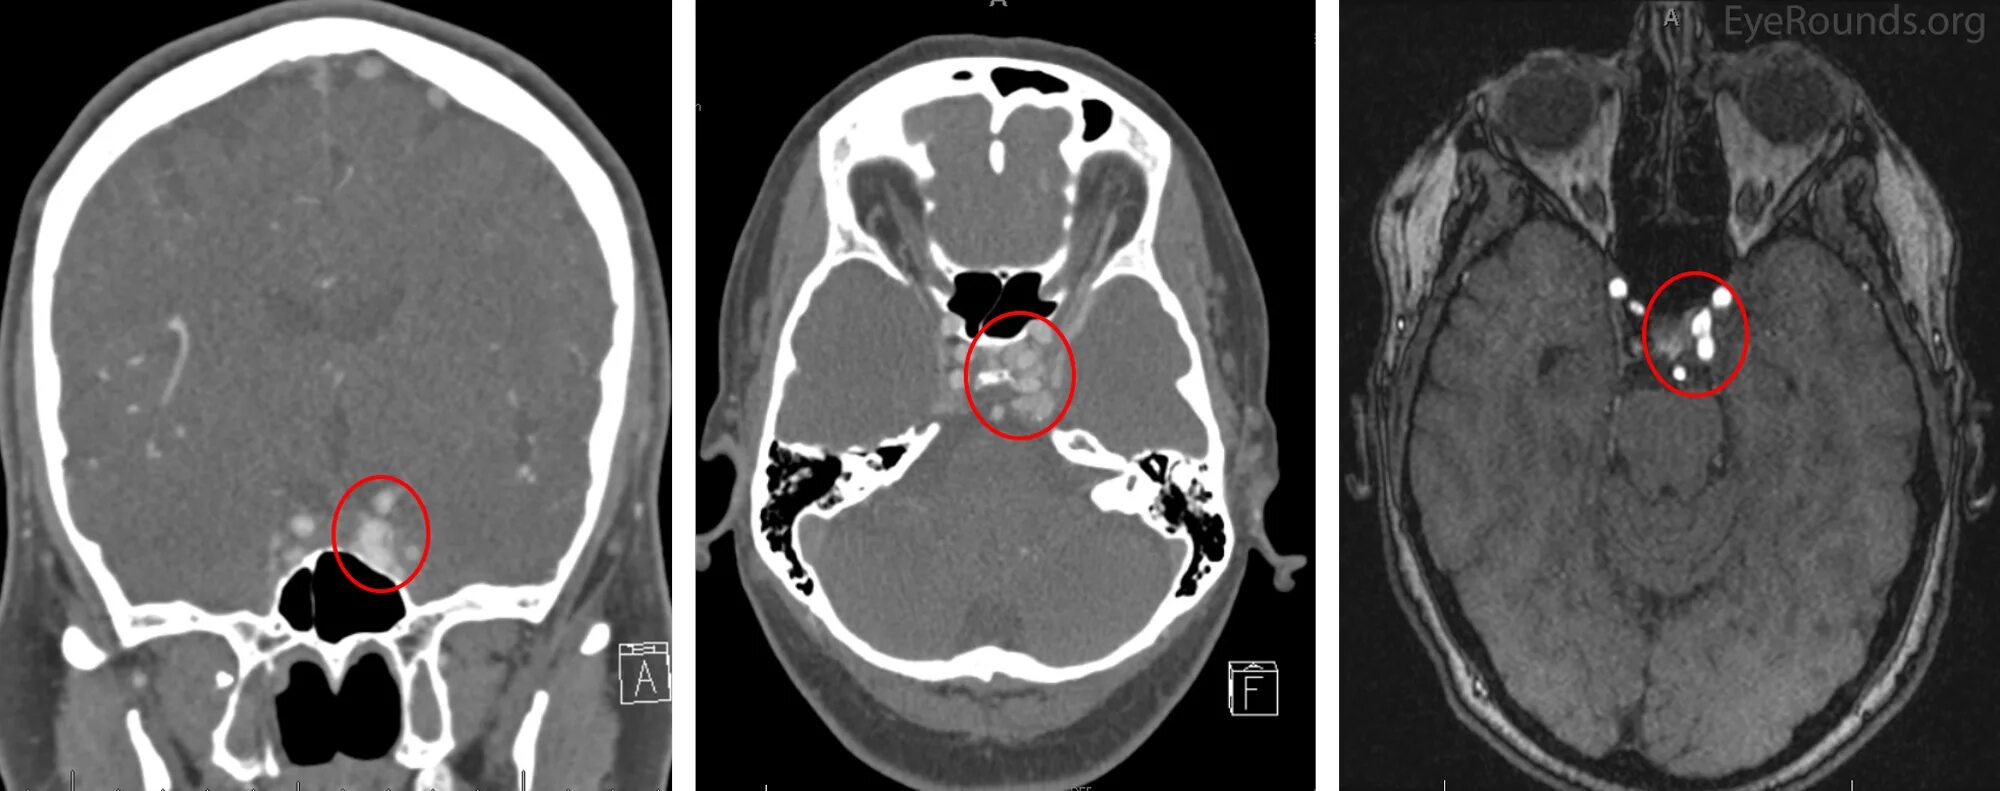

Pre operation